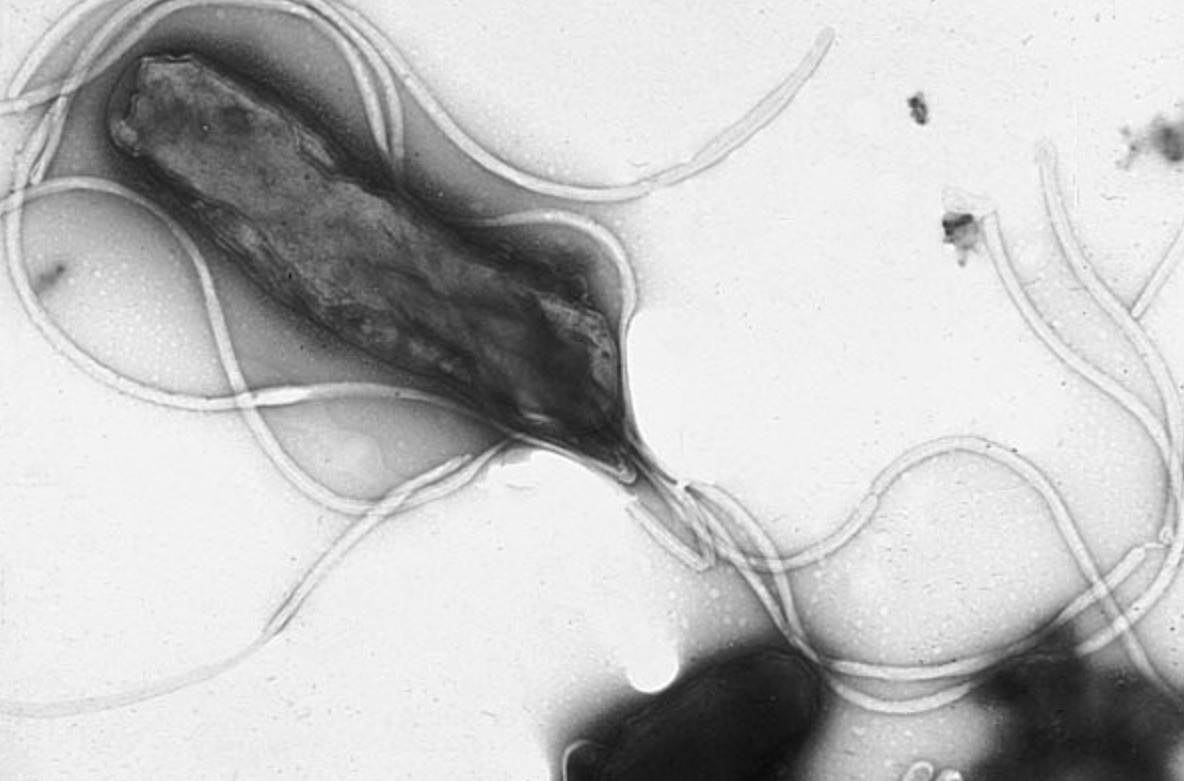

Marshall became interested in Warren’s findings and began a systematic investigation. Together, they studied biopsies from over a hundred patients and found a clear correlation: the bacterium, which would later be named Helicobacter pylori, was present in nearly all patients with ulcers. It turned out that this microorganism hides under the mucus layer protecting the stomach wall and produces an enzyme called urease, which neutralizes the acid around it. In simple terms, the bacterium created its own comfortable habitat in the most aggressive environment in the body.

The bacterium Helicobacter pylori under a microscope. Image source: wikimedia.org